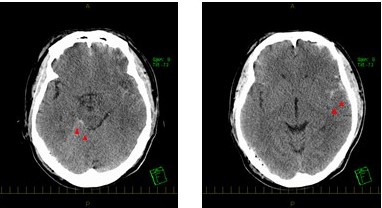

外傷性くも膜下出血のCT画像

くも膜下出血とは、脳を包む3つの膜のうち、2つ目の膜であるくも膜の内側に出血するものです。くも膜下出血の原因でもっとも有名なものは脳動脈瘤破裂によるものですが、外傷性くも膜下出血は、文字通り、頭部外傷が原因でくも膜の内側に出血するものです。

CTやMRIの検査と受傷起点から診断されます。脳動脈瘤の破裂の可能性やその他出血性の脳血管異常を否定するために脳血管の詳しい検査が必要になることもあります。稀に脳動脈損傷や脳梗塞を合併することもあります。